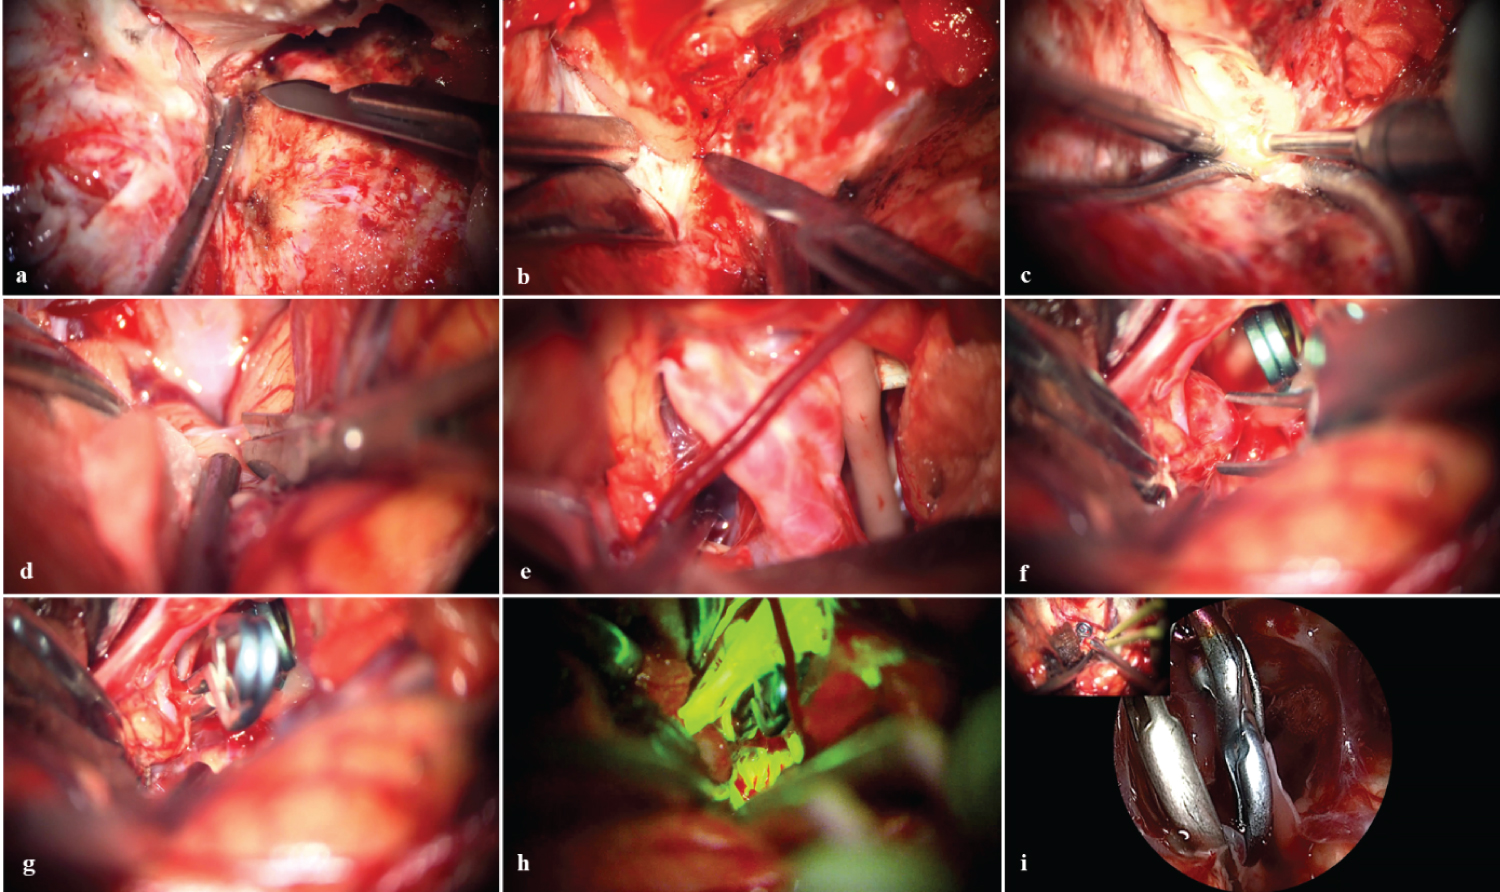

A right fronto-temporo-zygomatic craniotomy was performed (Figure 2), wide dissection of the Silvian fissure, proximal control with temporal clipping of the basilar artery, and identification and clipping of the aneurysm. We corroborated the permeability of the posterior brain and collaterals with fluorescein and reviewed with the endoscope the area that did not allow us to observe the microscope and rule out the possibility of an inadvertent clipping of collaterals (Figure 3).

Figure 3: Microsurgical vision. a) Exposure of the sphenoid wing and posterior drilling; b) Mini-peeling of the middle fossa; c) Anterior extradural clinoidectomy; d) Wide opening of the Silviano valley; e) ACI-III bifurcation nc; f) Temporary clipping in basilar artery; g) Clipping and exclusion of P1 aneurysm; h) Fluorescein videoangiography corroborates P1-P2 exclusion and patency; i) Endoscopic visualization confirms patent branches adjacent to the neck. View Figure 3

The use of fluorescein video angiography showed a direct relationship with a decrease in postoperative complications and higher success rates in surgeries [9,11]. In our case we allowed to verify the definitive clip je of the aneurysm, avoiding the adjacent vascular damage. Endoscopy allowed us to observe structures that are not accessible through the field of view offered by the surgical microscope [12].